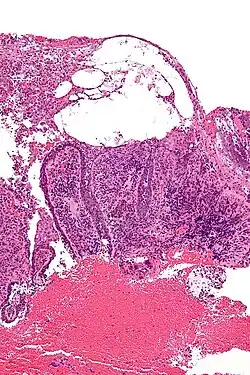

| Micrograph of pemphigus vulgaris with the characteristic "tombstoning". H&E stain. | |

Pemphigus is an autoimmune disease caused by antibodies directed against both desmoglein 1 and desmoglein 3 present in desmosomes. Loss of desmosomes results in loss of cohesion between keratinocytes in the epidermis, and a disruption of the barrier function served by intact skin. The process is classified as a type II hypersensitivity reaction (in which antibodies bind to antigens on the body's own tissues). On histology, the basal keratinocytes are usually still attached to the basement membrane leading to a characteristic appearance called "tombstoning". Transudative fluid accumulates in between the keratinocytes and the basal layer (suprabasal split), forming a blister that is easily dislodged when a lateral force is applied, resulting in what is known as a positive Nikolsky's sign.[6] This is a contrasting feature from bullous pemphigoid, which is thought to be due to anti-hemidesmosome antibodies, and where the detachment occurs between the epidermis and dermis (subepidermal bullae). Clinically, pemphigus vulgaris is characterized by extensive flaccid blisters and mucocutaneous erosions. The severity of the disease, as well as the mucosal lesions, is believed to be directly proportional to the levels of desmoglein 3. Milder forms of pemphigus (like foliacious and erythematoses) are more anti-desmoglein 1 heavy.